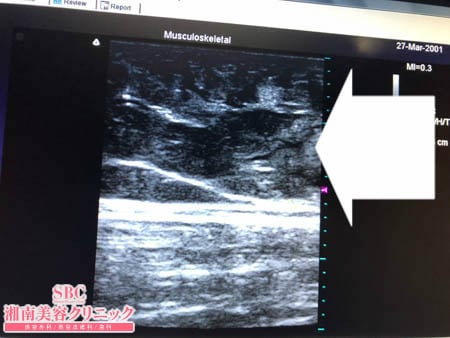

No.241998【脂肪吸引】【動画あり】湘南美容外科全ドクターの脂肪吸引最高責任者である竹田先生による脂肪吸引のフォトギャラリー!昔からコンプレックスな上に、最近10kg太ってしまいどうしようもなくなって脂肪吸引で確実に細くする!術中3Dタッチビュー・左太もも前面

2回わけの2回目は太もも前面の脂肪吸引になります。